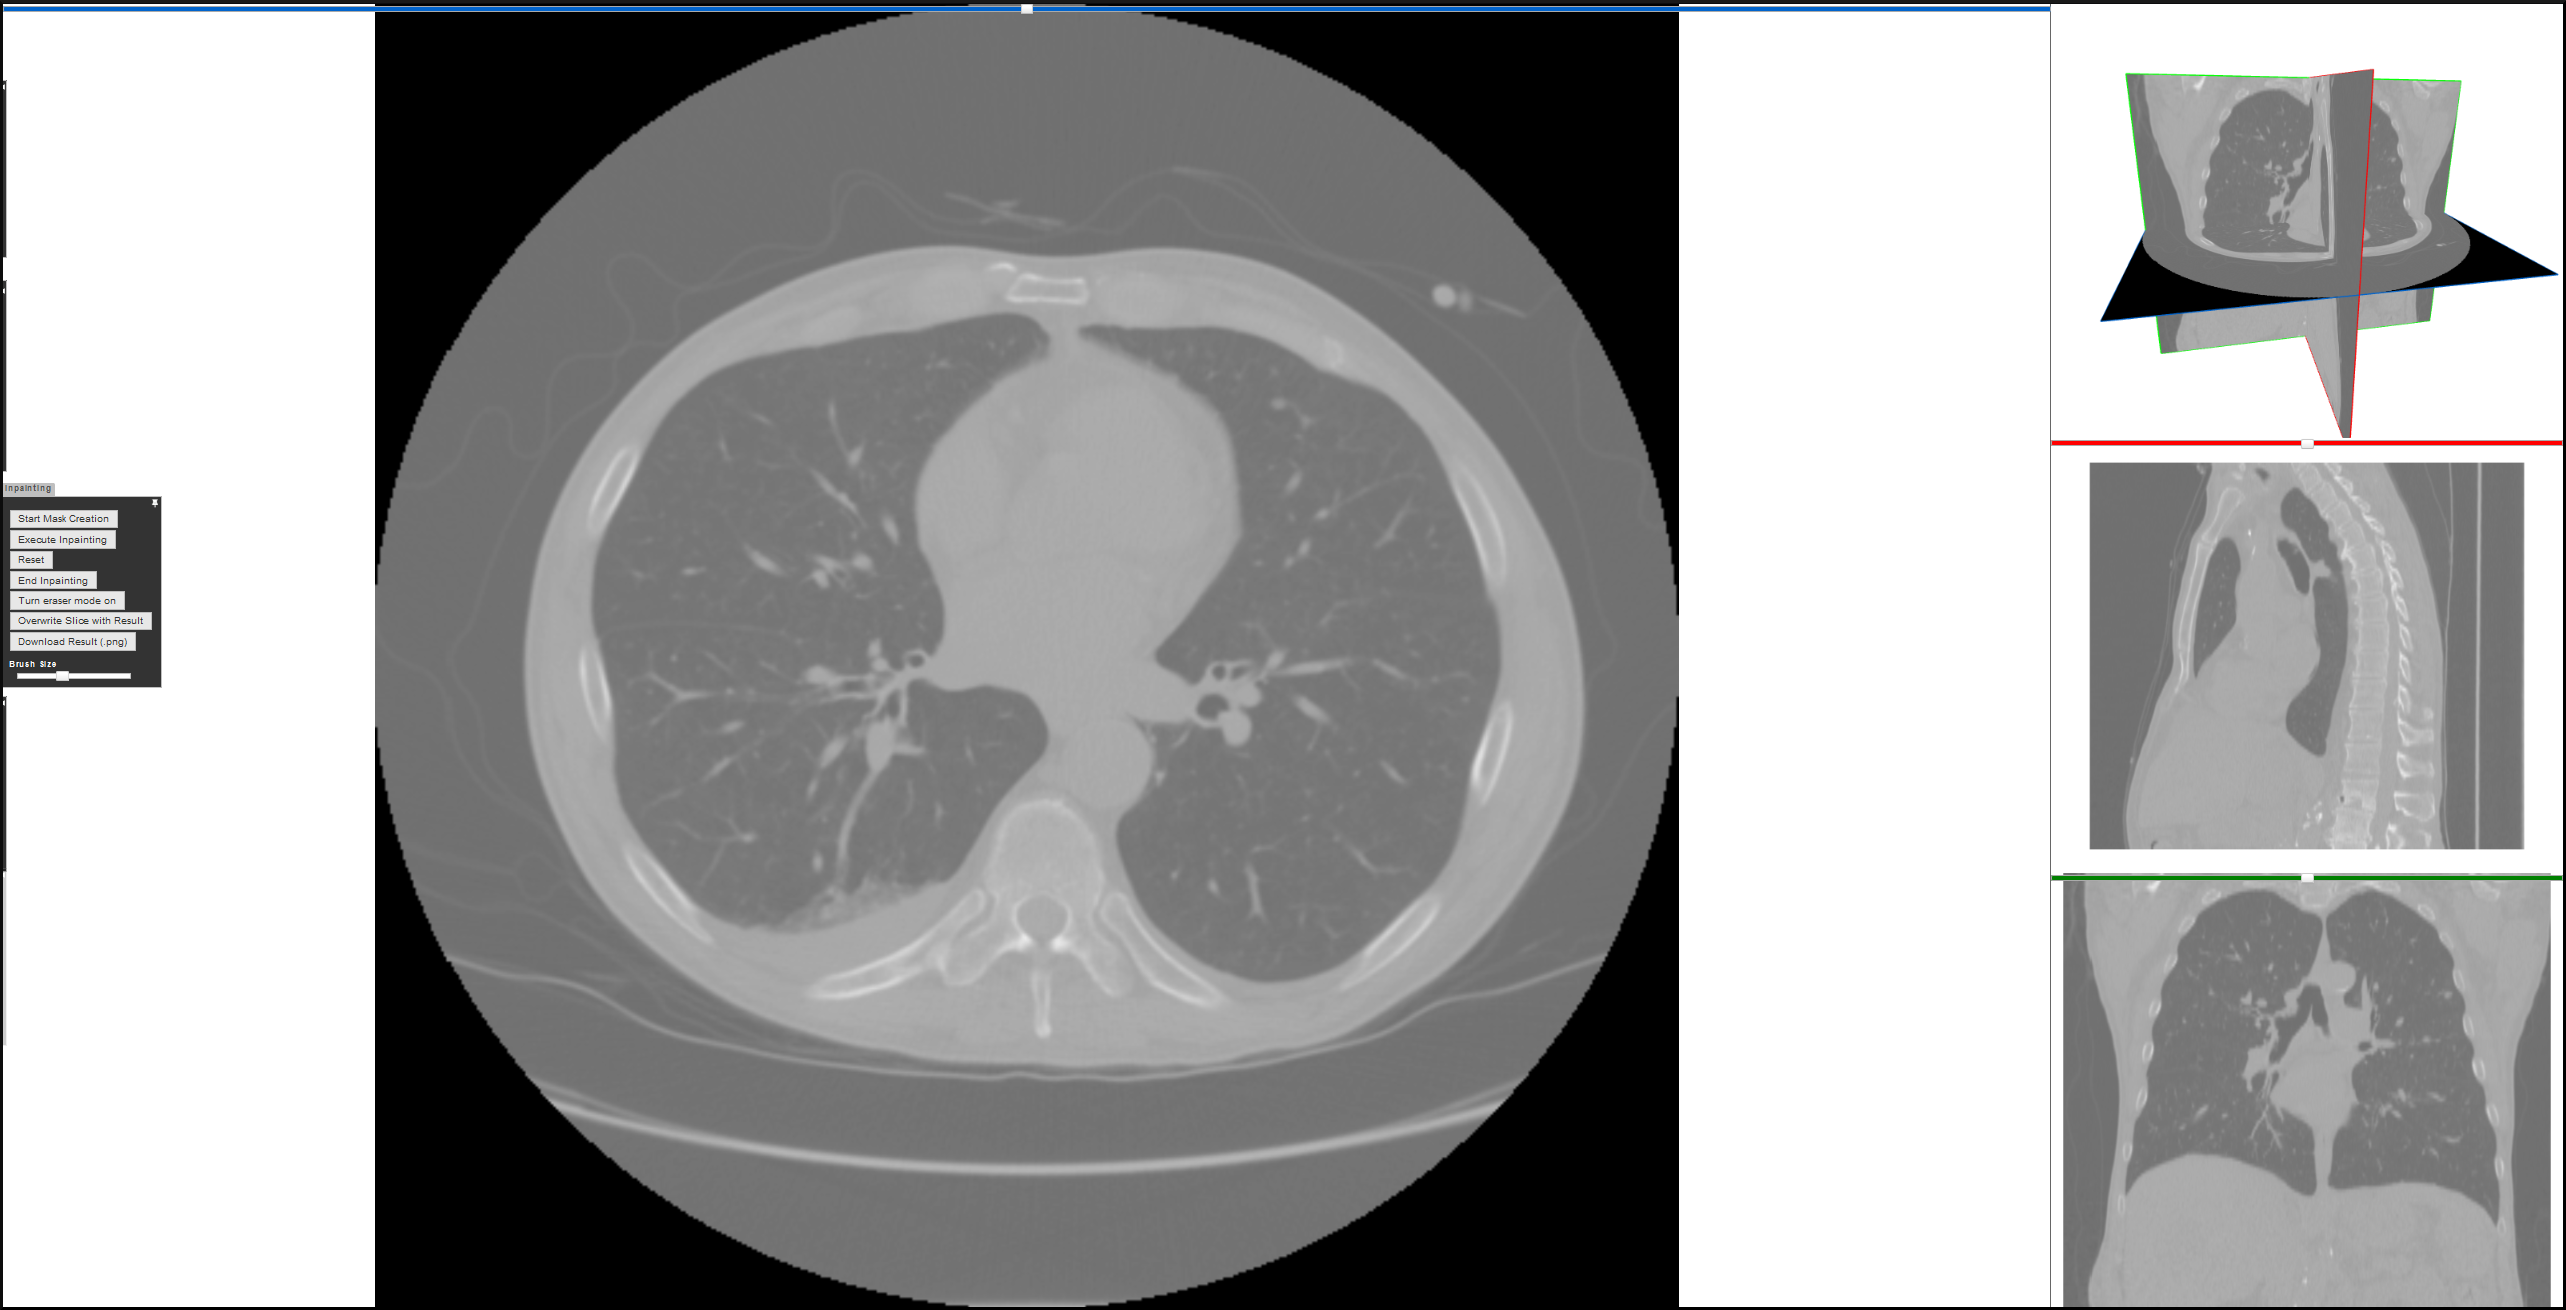

Refer to caption

Figure 1: Chest CTA scan slice featuring an aortic dissection. The aorta can be recognized as a circular shape in the center of the image (just above the spine). The aortic dissection is visible as a dark line separating this circular shape.

Figure 2: Current layout of the Medical 3D Viewer on the StudierFenster website with activated inpainting tab in the sidebar menu (on the left side).

Figure 2 shows the layout of the Medical 3D Viewer on StudierFenster. The current configuration of the Medical 3D Viewer features four views. Three of them are positioned on the right-side. The fourth one is larger than the others and, hence, is the primary view. In these four views the same CT scan volume is displayed in four different perspectives: a slice in each sagittal plane (from the side), coronal plane (from the front) and axial plane (from the top), as well as a three dimensional rendering, where all three planes are displayed. By clicking on one of the smaller views, the main view can be freely switched. The UI controls for the different operations on input data, like segmentation and inpainting, are located in a sidebar menu.